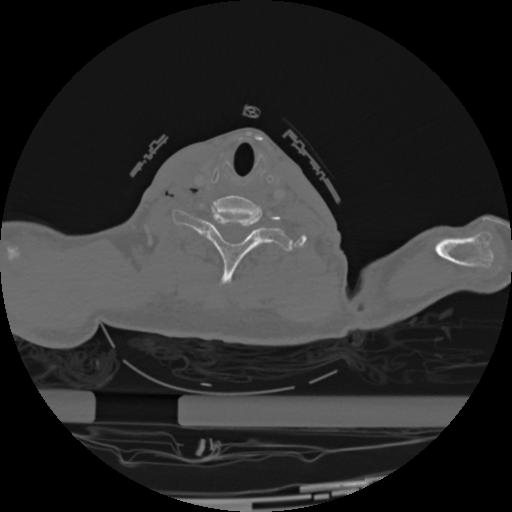

22 ANGIO,CE,Vol,0.5,ANGIO,,